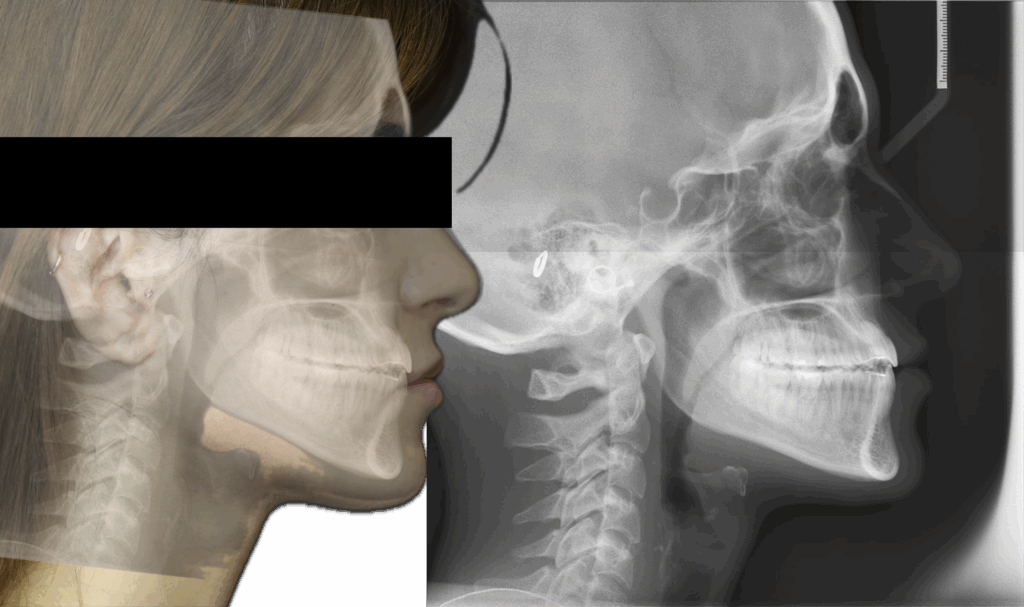

A 22-year-old female patient presented with a Class III malocclusion. She does not like her own profile. Her facial profile was straight with a slightly retrusive maxilla, the upper incisors were within normal inclination, and the lower incisors were retroclined. Bolton discrepency is on mandible for 6 teeth. A retruded upper lip and a normally positioned lower lip were noted. There was also a marked lack of midface support, and the constricted dental arches resulted in a narrow smile and pronounced dark buccal corridors.